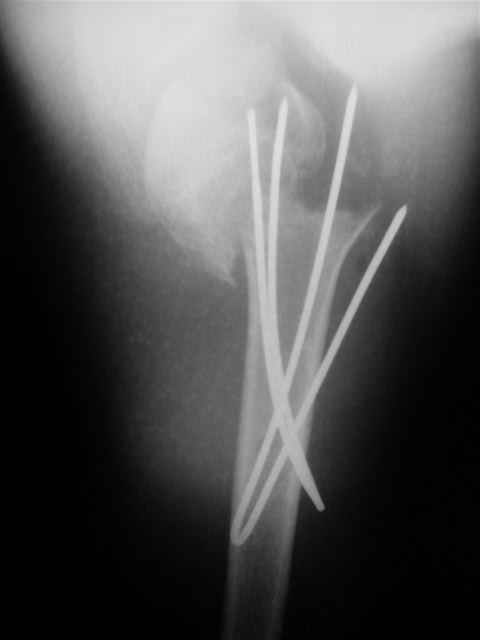

Клинические снимки - 3 недели после операции

с уважением М. Беренштейн

Посылаю послеоперационные Рг граммы.

Всего Доброго,

Евгений И Чекашкин

Отправитель: Alexander Chelnokov 02 Декабрь 2004, 19:21

|

Поздравляю, получилось просто замечательно. Если можно, расскажи чуть подробнее, как делали - как вправляли, как вводили спицы, поворачивали ли их?

Спасибо за поздравления:-))

Я и сам доволен результатом. В предпоследнем письме я кратко описал ход операции - закрыто репонировать не удалось( 2 недели с момента травмы и 1 неделя после неудачной репозиции) после удаления пучков спиц, пришлось сделать - 2см разрез на уровне перелома и с помощью периостального элеватора (золотое правило механики) *одеть* головку на дистальный отломок.

Спицы проводил через старые отверстия, вращая пучок импактором- направителем при его введении в головку.

Твоя идея с дистрактором и разборным направителем от ЛОРиков просто замечательны, в следующий раз надо будет у них позаимствовать воронку для риноскопии, предварительно срезав торцевую часть для лучшего контакта с костью.

Спасибо за дискуссию - была очень полезна для меня, надеюсь, что следующий случай в техническом плане будет лучше подготовлен и выполнен.